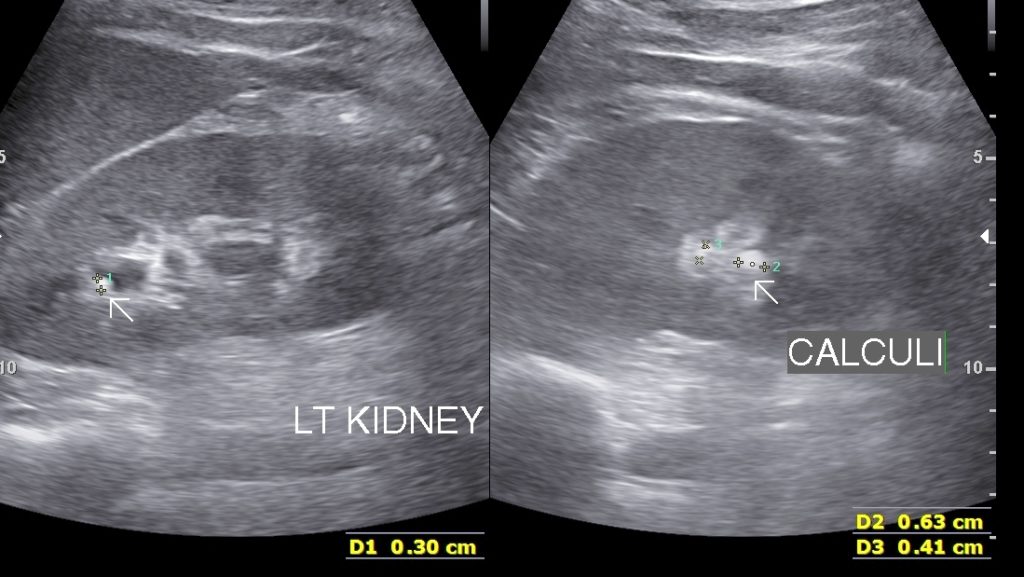

• Renal Calculi: